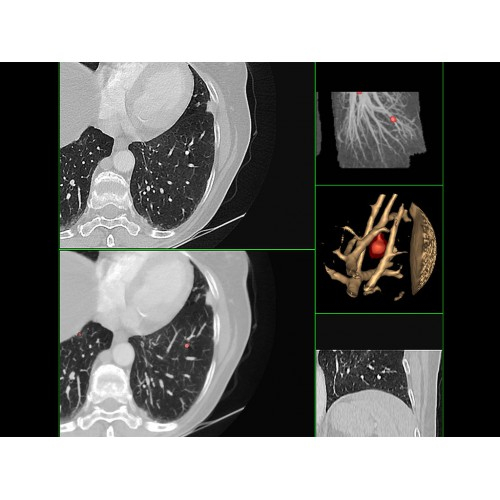

Кардиология

• Неинвазивная оценка состояния коронарных артерий.

• Диагностика атеросклероза и других сердечно-сосудистых патологий.

Онкология

• Раннее выявление новообразований и контроль эффективности лечения.

• Планирование лучевой терапии с высокой точностью.